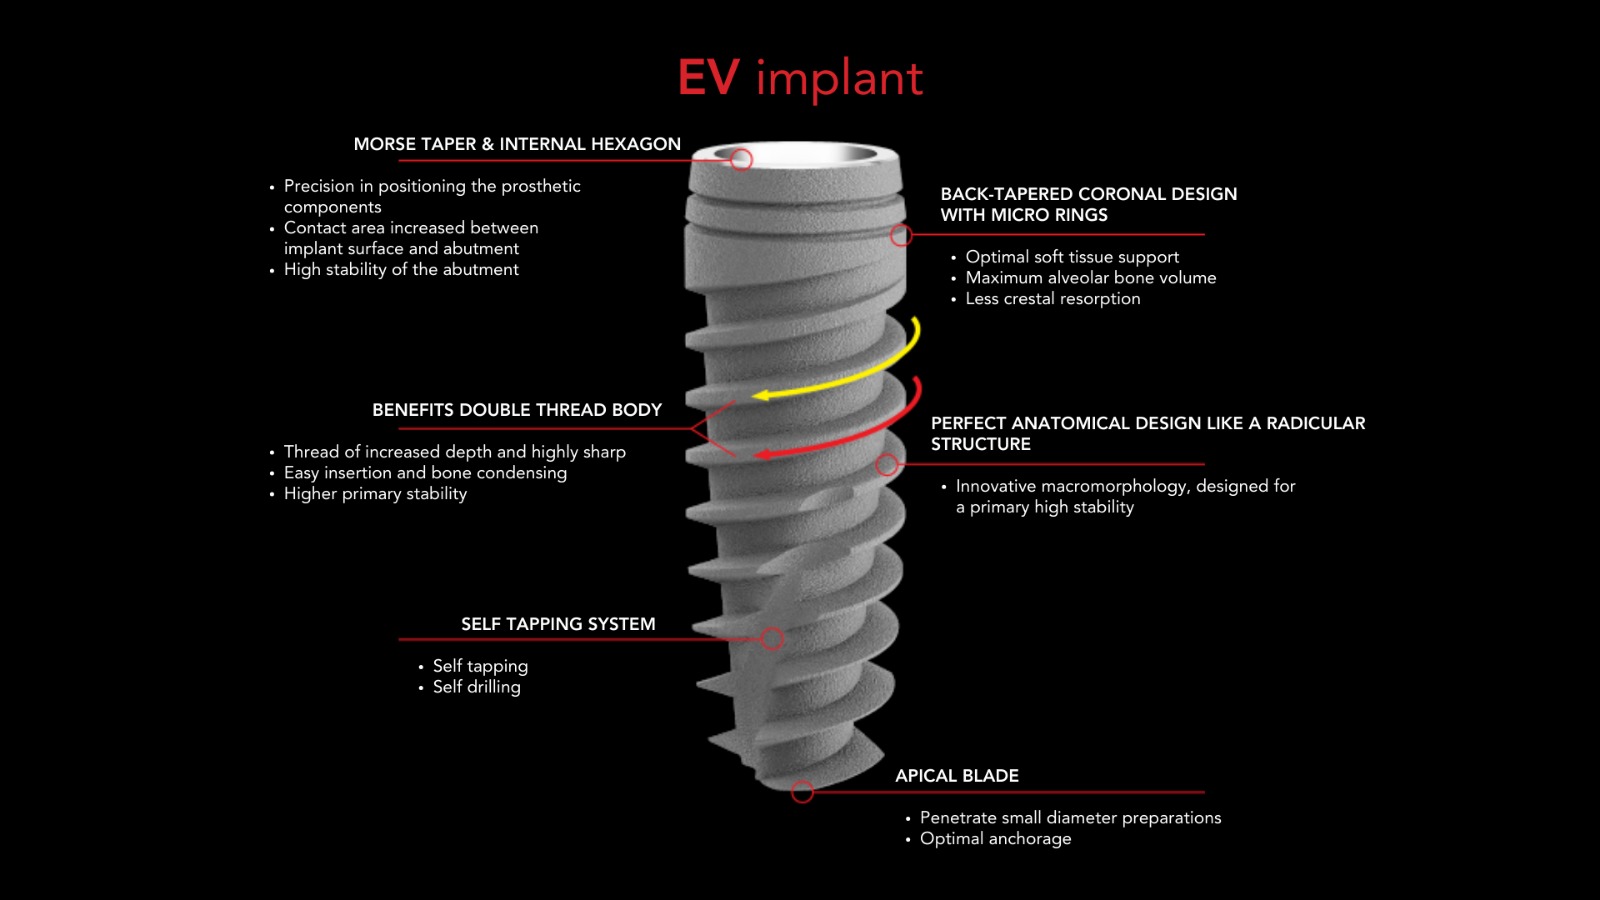

Advanced EV Implant System

Designed for immediate load

with functional Prosthesis.

Shorter Time to Teeth.